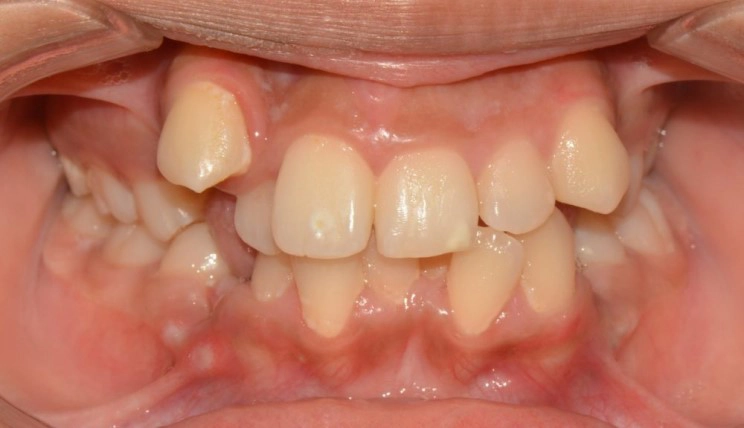

Phase I Treatment

Interceptive treatment for young patients (6-10 years old): Early treatment can be in a patient’s best interests if their problem is one that could become more serious over time if left untreated. - Intercept the developing problem; Eliminate the cause; Guide the growth of facial and jaw bones; Provide adequate space for incoming permanent teeth.

Patient Information:

Age: 9

Gender: Male

Invisalign Treatment Option: Invisalign Teen with MA

Total Treatment Time:

13 months